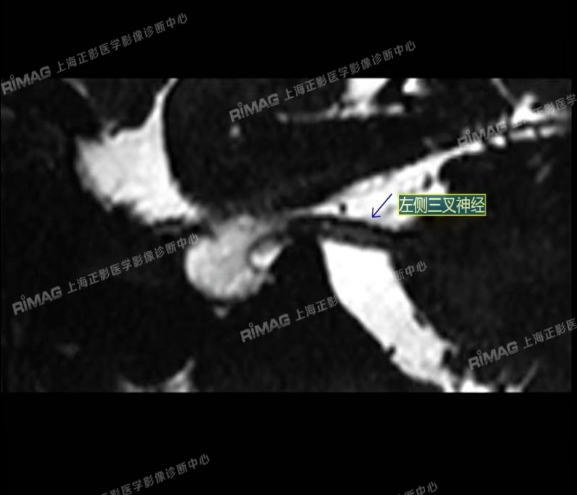

本例患者接受了MRTA(磁共振体层成像脑血管显影术)检查。这是一种非常精细的磁共振成像技术,能够清晰显示脑神经与周围血管的立体关系,尤其适用于三叉神经痛的病因诊断。

影像表现:右侧三叉神经根部外下方见小血管斜跨,与三叉神经分界不清;左侧未见明显异常(对照)。